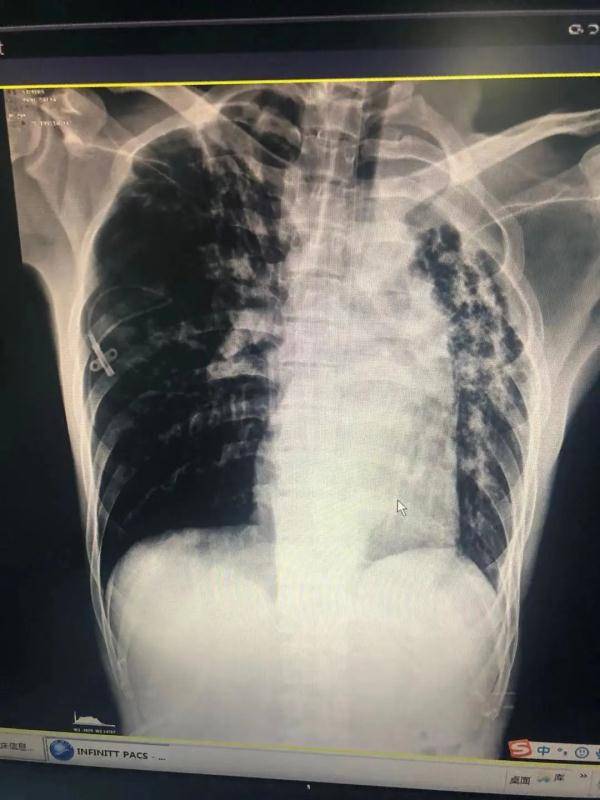

CT显示患者右肺压缩 , 左肺堵塞 。

此时CT检查显示 , 小杨右侧气胸 , 右肺犹如被戳破的气球 , 瘪了 , 肺组织压缩达70% 。 此外 , 两肺结核(空洞形成)继发性支气管扩张、左上肺萎陷;右中下肺渗出性改变 。 若不及时抢救会危及生命 。